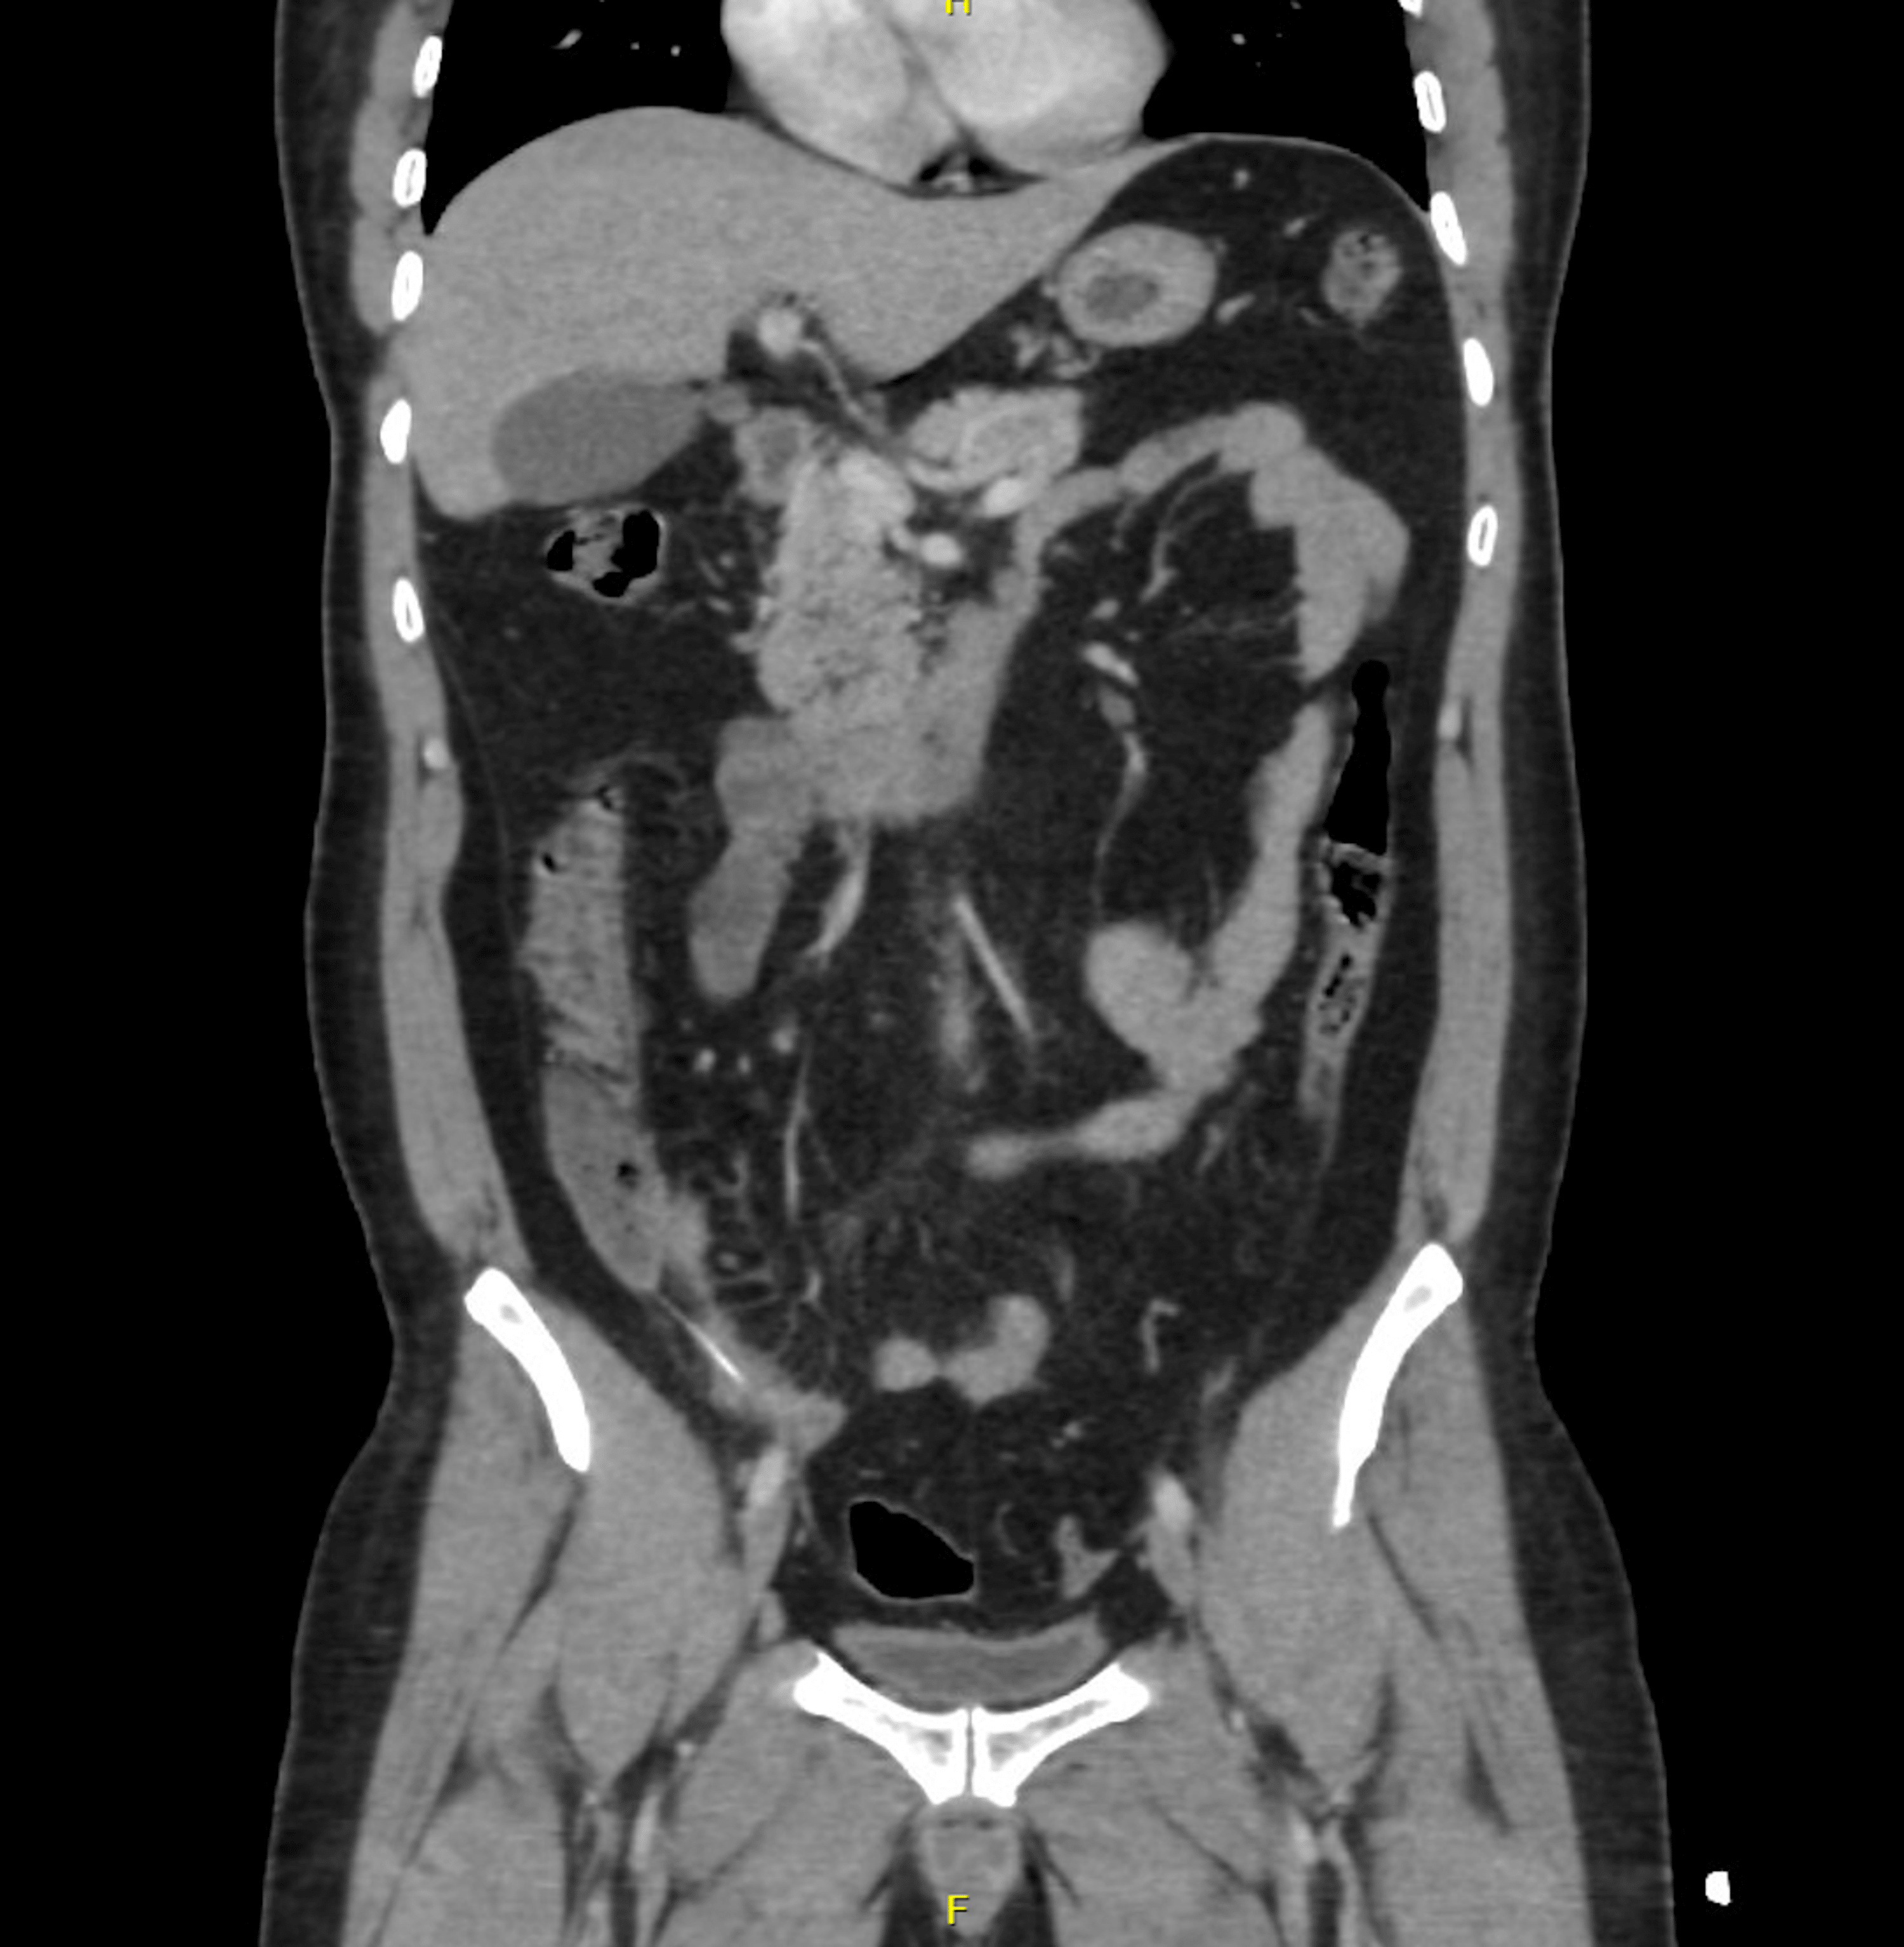

Abdominal CT bowel perforation • LITFL • Radiology Library Causes Of Bowel Perforation An overview of the clinical features, diagnosis, and management of the patient with alimentary tract perforation is reviewed here. The contents in your colon can leak out through the hole caused by a perforated bowel. There are three main causes of a perforated bowel: The most common form of bowel perforation trauma is an accidental injury to the. It can. Causes Of Bowel Perforation.

Abdominal CT bowel perforation • LITFL • Radiology Library Causes Of Bowel Perforation There are three main causes of a perforated bowel: Gastrointestinal perforation (gp) occurs when a hole forms all the way through the stomach, large bowel, or small intestine. This can cause bleeding, as well as a painful and serious infection. This condition can easily develop into serious. Bowel perforation results from insult or injury to the mucosa of the bowel. Causes Of Bowel Perforation.

Abdominal CT bowel perforation • LITFL • Radiology Library Causes Of Bowel Perforation It can be caused by several different conditions,. The most common form of bowel perforation trauma is an accidental injury to the. An overview of the clinical features, diagnosis, and management of the patient with alimentary tract perforation is reviewed here. Intestinal perforation, defined as a loss of continuity of the bowel wall, is a potentially devastating complication that may. Causes Of Bowel Perforation.